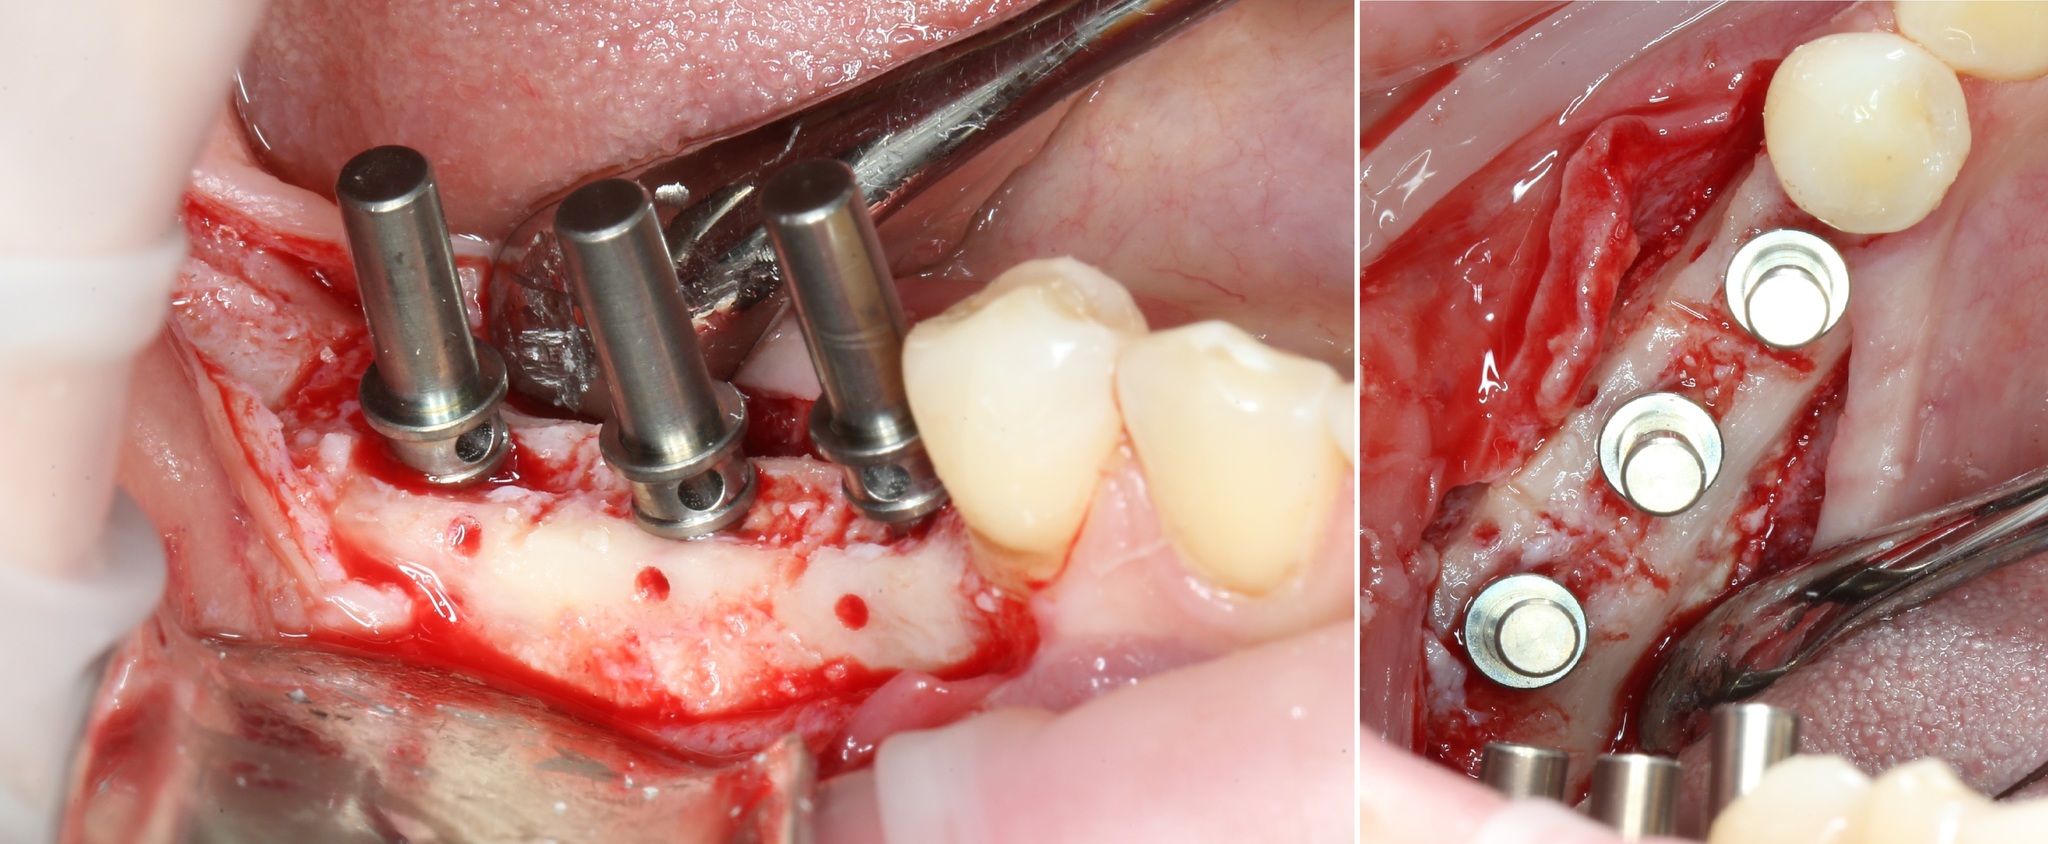

Разметка под имплантаты:

Вкратце, при помощи пинов проводится проверка параллельности:

Устанавливаются имплантаты:

И «глушатся»:

Операция, классически, заканчивается наложением швов: